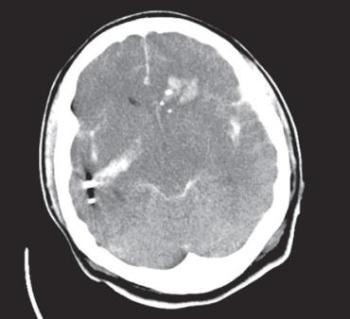

A túlnyomás okozta sérülés legsúlyosabb tünetcsoportja az ún. robbanásos tüdő (blast lung), mely klinikailag apnoe, bradycardia és hypotensio triászának képében nyilvánul meg. A robbanásos tüdő képe az esetek egy részében a robbanást követően azonnal, más részében 12–48 órával később alakul ki. A leggyakoribb halálok a robbanást kezdetben túlélők között a robbanásos tüdő kialakulása. Mellkasi AP röntgenfelvételen kétoldali, jellegzetes pillangó alakú elváltozás észlelhető [107].

16.1. ábra. Robbanásos tüdő (blast lung) CT képe (a szerző felvétele)